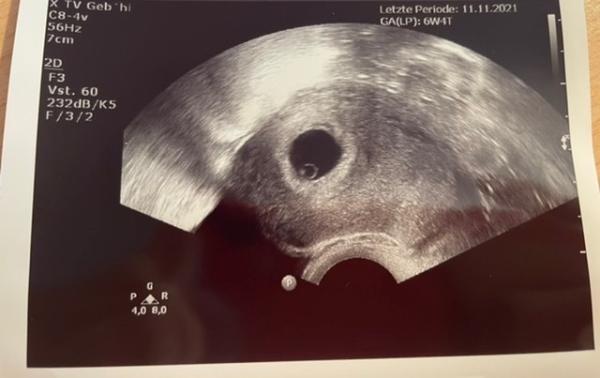

Guten Morgen ihr Lieben Vor 2 Wochen wurde per Ultraschall meine Schwangerschaft festgestellt und ich sollte heute erneut kommen, um den Mutterpass zu erhalten. Nun konnte der Herzschlag nicht eindeutig festgestellt werden. Genau gesagt schlug da nur ganz kurz etwas aus, danach nix mehr. Das hat meiner Ärztin nicht gereicht und ich soll in 7 Tagen erneut kommen, dann bei 7+4. Ich hab jetzt nicht direkt Angst, aber etwas verunsichert bin ich schon. Immerhin habe ich schon fest mit mehr gerechnet heute. Aber man erkennt gut den Dottersack, und es ist keine ELSS Ist euch das auch passiert?